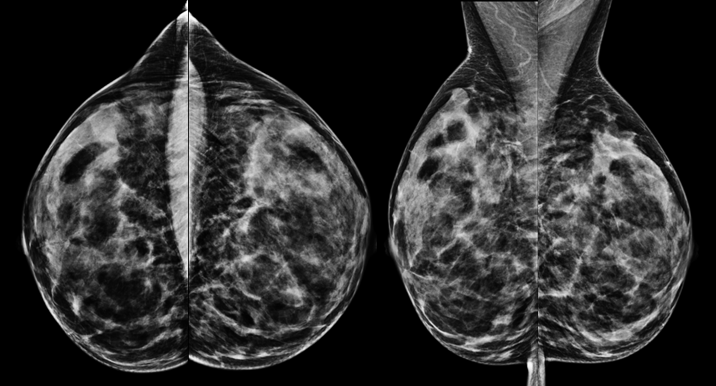

Mammographie einer 52jährigen Patientin zur Brustkrebsfrüherkennung

Bei der Mammographie entsteht das Bild entweder durch Belichtung eines Röntgenfilms (Film-Folien-Mammographie) oder mit Hilfe eines digitalen Bilddetektors (digitale Mammographie). Beide Systeme erreichen eine ähnliche Bildqualität. Studien haben gezeigt, dass bestimmte Veränderungen (Mikrokalk) etwas besser mit der digitalen Technik dargestellt werden können. In der Universitätsklinik Tübingen sind zwei digitale Mammographie-Systeme installiert, Film-Folien-Systeme werden nicht mehr verwendet. Die zwei zur Verfügung stehenden Mammographiegeräte bieten außerdem die Möglichkeit, eine Schichtbildmammographie, die sogenannte Tomosynthese, durchzuführen. Mit dieser Technik können gutartige Befunde besser von bösartigen Befunden differenziert werden.

Eine weitere Mammographie-Technik, die an unserer Universitätsklinik durchgeführt wird, ist die kontrastmittelangehobene Mammographie. Sie ist – insbesondere, wenn eine Kernspintomographie (s.u.) aus bestimmten Gründen (z.B. Angst in engen Räumen) nicht durchführbar ist – eine hilfreiche Methode, um auffällige Veränderungen in einer dichten Brust, also einer Brust mit viel Drüsengewebe, zu detektieren. Da die Mammographie eine Röntgenuntersuchung ist, sollte sie nur durchgeführt werden, wenn die Untersuchung medizinisch begründet ist, um eine unnötige Anwendung von Röntgenstrahlen zu vermeiden. Jüngere Frauen (vor dem 40. Lebensjahr) sollten daher nicht ohne eine entsprechende medizinische Begründung mammographiert werden. Ab dem 50. Lebensjahr überwiegt der Nutzen der Mammographie deutlich gegenüber den wenig wahrscheinlichen möglichen Schäden durch die applizierte Strahlung.